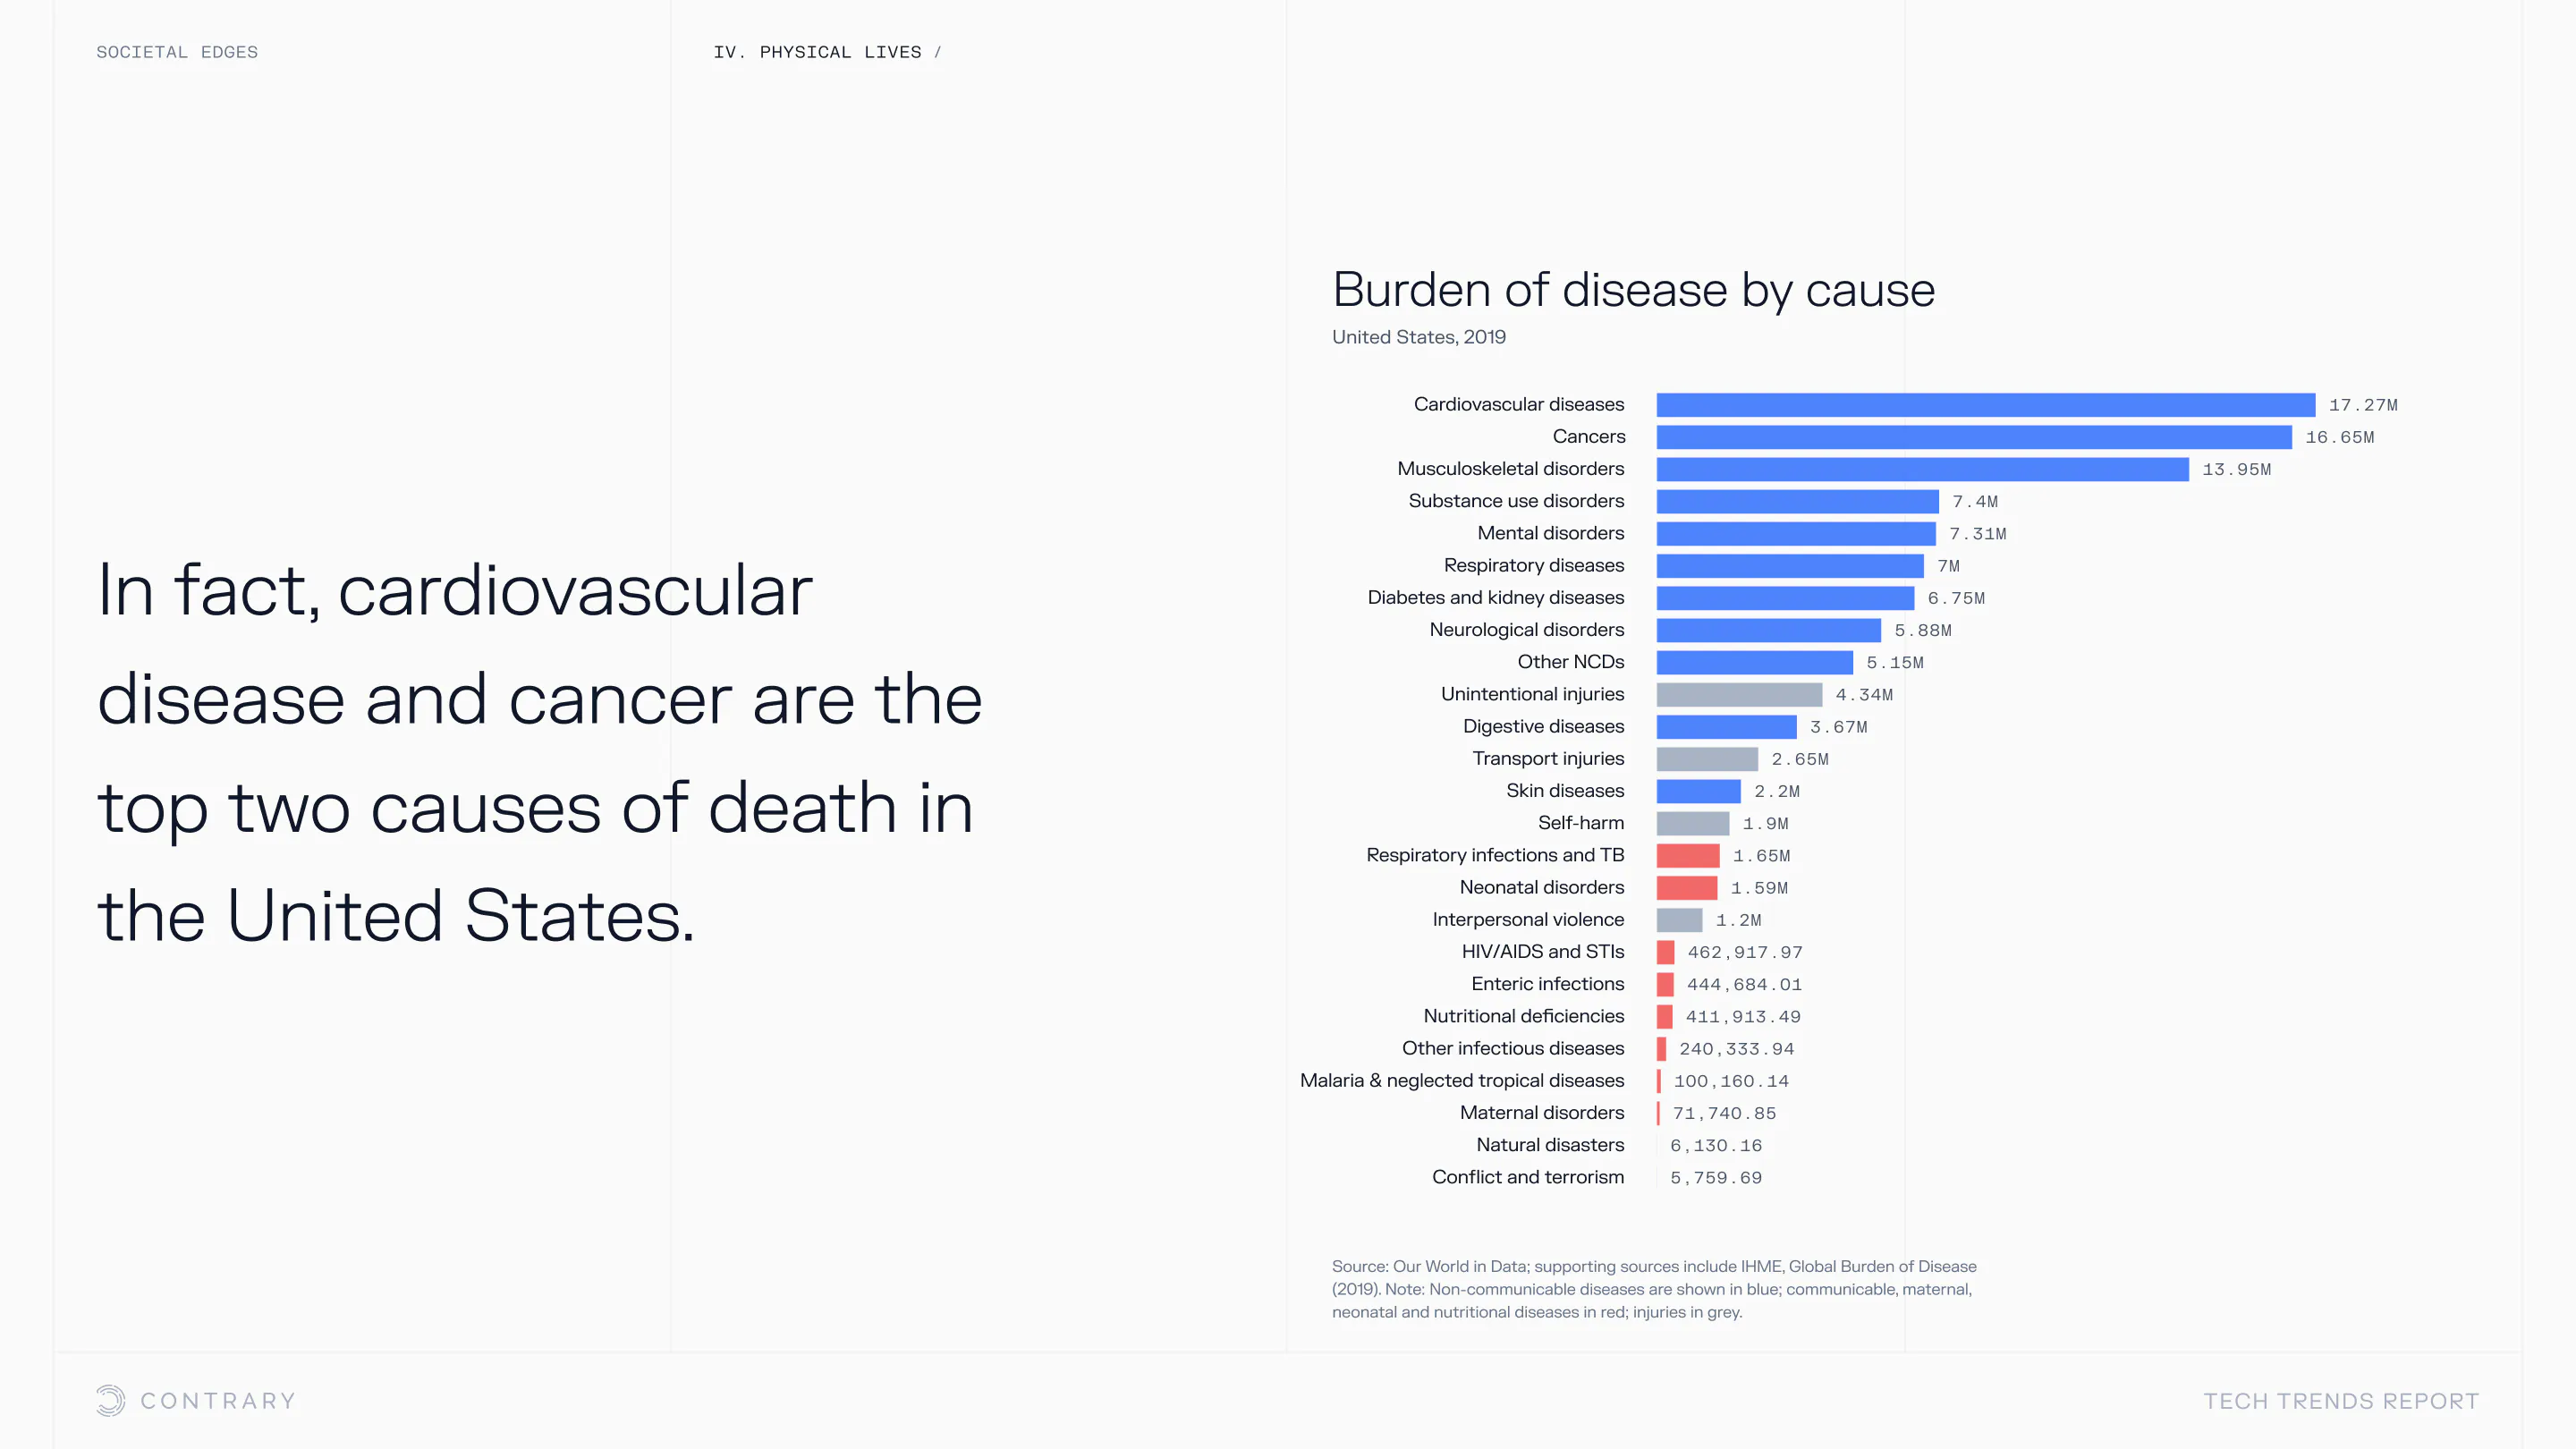

An aging population is bringing up a range of increased concerns, from mental health to disease control. Obesity and gastrointestinal cancers are plaguing younger generations. The cutting edge is tackling a system that has unhealthiness woven into it.